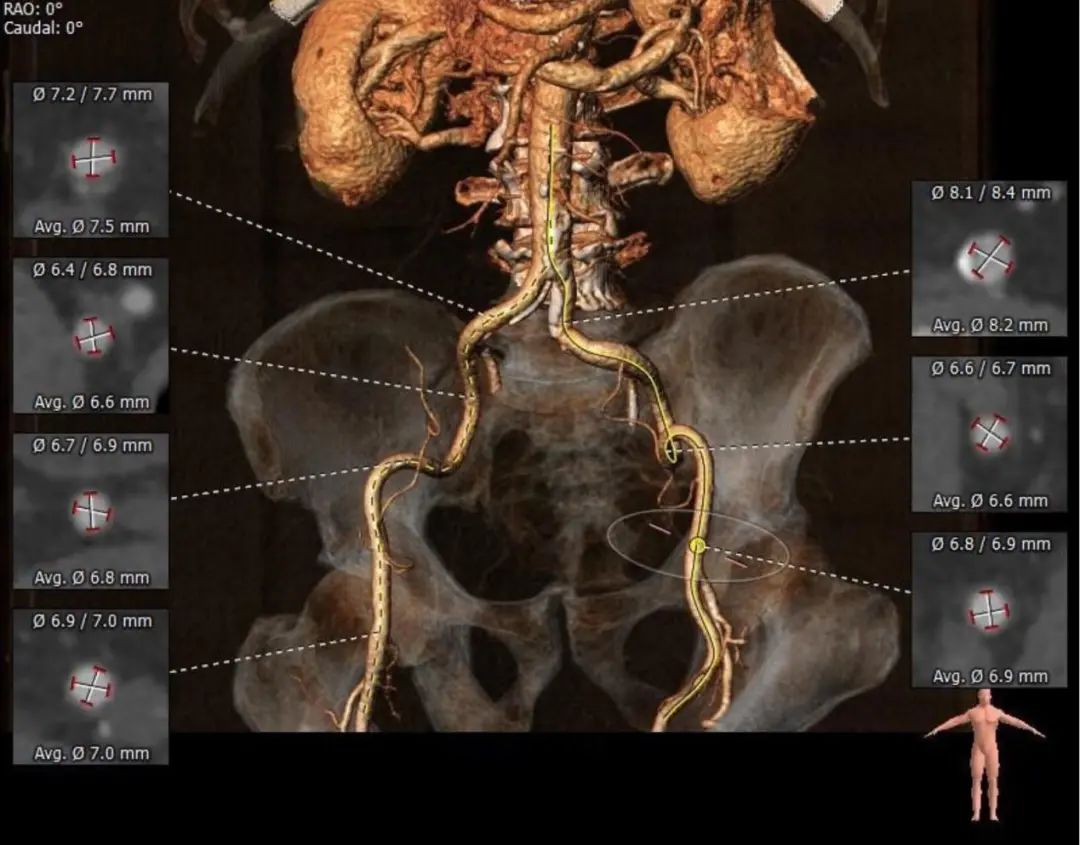

术前CT检查

主动脉根部评估

术前CT:三窦氏主动脉瓣,主动脉瓣SAVR术后,SMVP术后,二尖瓣人工瓣环距主动脉瓣环约5mm;瓦式窦内径尚可,窦管交界、升主动脉内径可。

左心室解剖评估

左心室心腔稍偏小,可能会出现急性大量主动脉瓣反流而导致低血压甚至循环崩溃的风险。

入路评估

外周入路血管散在钙化,双侧入路血管管径良好,整体入路血管条件尚可。